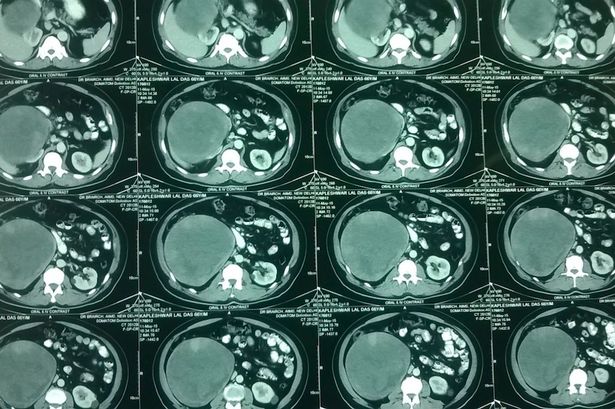

(ĐSPL) - Một người đàn ông đã khiến các bác sĩ kinh ngạc khi phát hiện ra khối u khổng lồ nặng 5kg.

Kapleshwar Lal Das, 66 tuổi đến từ

Phát hiện ra khối u khổng lồ to bằng quả dưa hấu trong bụng ông Kapleshwar. |

Ông Kapleshwar lập tức được đưa vào phòng phẫu thuật để cắt bỏ khối u khổng lồ.

Ca mổ kéo dài 5 giờ để cắt bỏ khối u an toàn. Nó nặng gấp nhiều lần một khối u thông thường, bám chặt vào gan và đại tràng.

Phẫu thuật tách khối u phải cắt thận cấp tiến đã được thực hiện cùng với mổ các hạch bạch huyết.